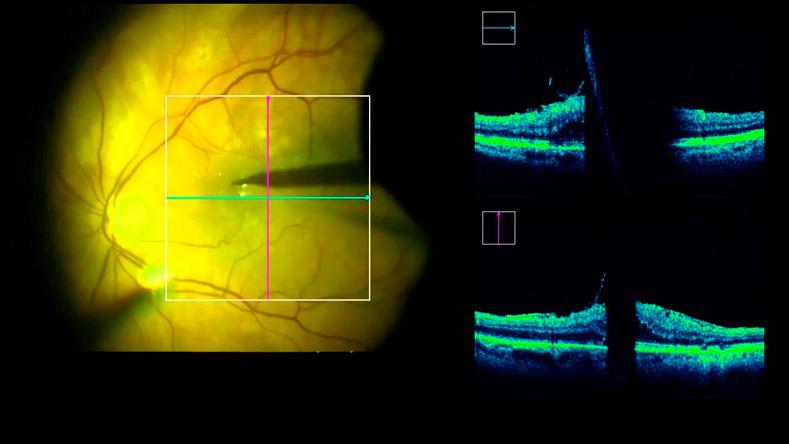

Звернувшись до нас, ви отримаєте повний комплекс офтальмологічних послуг! Вас вислухають, підтримають і додадуть оптимізму! Під час обстеження ми оцінюємо понад 120 діагностичних параметрів, враховуємо ваш спосіб життя, характер професійної діяльності та звички і складаємо реальну картину корекційних потреб. Дані про ваш стан зберігаємо в базі клініки, щоб відстежуваи зміни з точністю до кількох мікрон протягом тривалого періоду. Такі зміни для вас непомітні, але для нас це можливість визначити небезпечні ознаки захворювання ще до зниження зорових функцій.

Мікрохірургія ока — наша безпосередня сфера діяльності, яку ми розвиваємо! 30 років досвіду дозволяє нам повертати зір навіть після тривалої сліпоти. Якщо ви маєте хронічні патології ока, вам запропонують малоінвазивні втручання і пильний нагляд, що поліпшуватиме і зберігатиме зір на роки. Ми подбаємо про вашу впевненість у подоланні хвороби, і ви насправді відчуєте нову якість життя із ясним зором!

- Маємо 30 років досвіду діагностики та лікування рідкісних патологій очей.

Діабетична ретинопатія